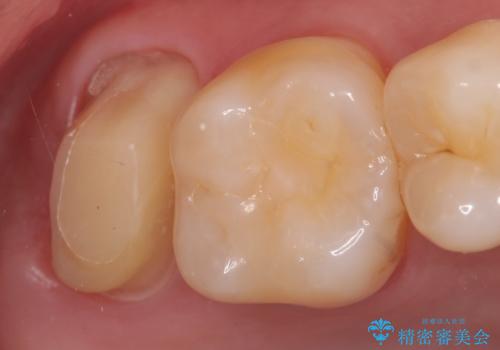

- 右上7の虫歯が大きく、他院にて抜歯と言われたが、なんとか残せないかと当院にいらっしゃった方の症例です。

自発痛の既往および持続痛を認めたため、カリエス除去後根管治療を行いました。

その後オールセラミッククラウンによる補綴を行いました。